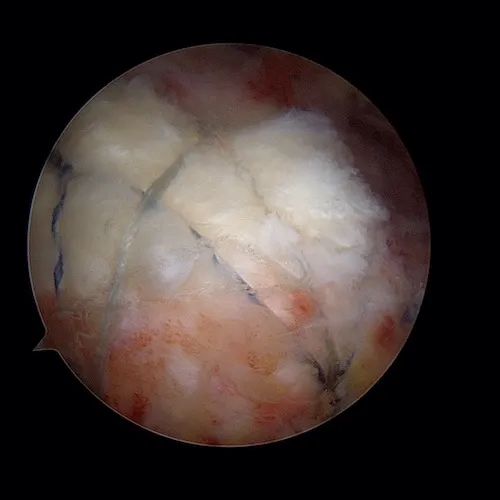

Le tendon est ensuite réparée après passage des sutures au travers du tendon. Une deuxième rangée d'ancres permet de plaquer le tendon contre l'os.

La cicatrisation tendineuse nécessite 6 à 8 semaines.